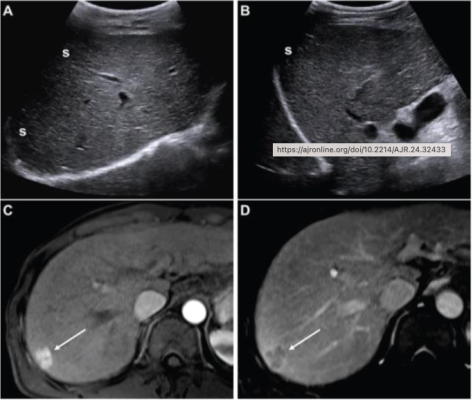

51-year-old man with hepatitis B-related cirrhosis, undergoing HCC surveillance: (A,B) Images from initial ultrasound examination. No suspicious lesion was identified, and examination received consensus ultrasound category of US-1. Nearly entire liver is visualized, with minimal shadowing (“s”, A and B), and examination received consensus result of VIS-A. AFP level was 7.1 ng/mL on assessment 6 months before ultrasound examination, 9.1 ng/mL on assessment 3 months before examination, and 14.2 ng/mL on assessment on day of examination. AFP result was thus assessed as positive based on progressive increase on two consecutive tests. Patient was considered to have negative surveillance result according to LI-RADS Ultrasound Surveillance version 2017, but positive surveillance result according to LI-RADS Ultrasound Surveillance version 2024. (C-D) Axial arterial-phase (C) and portal-venous phase (D) T1-weighted images from subsequent gadoxetic acid-enhanced MRI. MRI shows 2.0-cm arterial-phase hyperenhancing observation (arrow, C) with portal-venous washout (arrow, D) in segment 7. This observation was classified on MRI as LR-5, thus meeting present study’s reference standard for diagnosis of HCC. Mass is located in periphery of liver, an anatomic area where ultrasound visualization can be challenging due to shadowing.